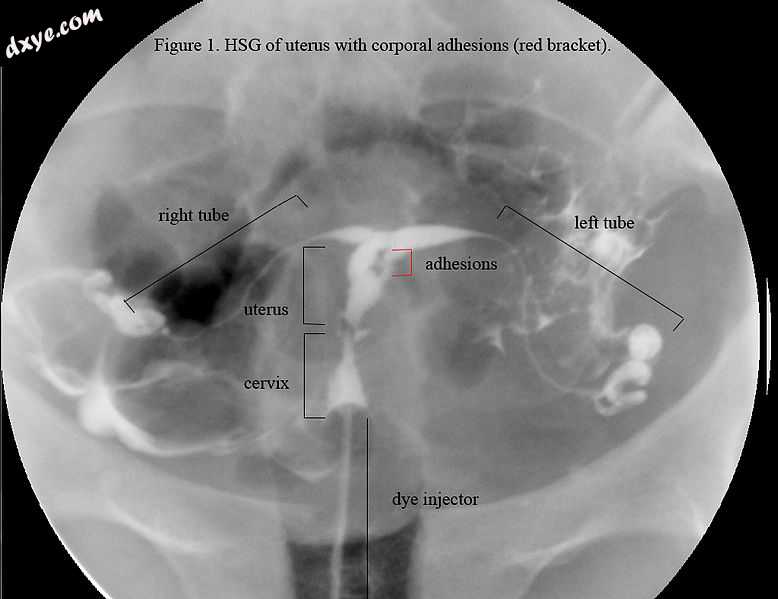

HSG view. Note not the same uterus as in ultrasound or hyst.jpg

HSG视图。 注意:子宫不同于超声或宫腔镜检查的子宫; 这个子宫看起来是T形的。

典型的是发生妊娠事件,然后进行D&C导致继发性闭经或月经少的病史。宫腔镜检查是诊断的金标准。[13]通过超声宫腔造影或子宫输卵管造影成像可以揭示瘢痕形成的程度。超声不是诊断阿舍曼氏综合症的可靠方法。激素研究显示正常水平与生殖功能一致。

必须进行后续检查(HSG,宫腔镜检查或SHG),以确保粘连没有重新形成。为了恢复正常的子宫腔,可能需要进一步手术。根据最近对61例患者的研究,粘连复发的总率为27.9%,严重者为41.9%。[26]另一项研究发现,术后粘连再次发生于近50%的严重AS和21.6%的中度病例中。[13]与中度到严重的粘连不同,轻度IUA似乎没有改变。